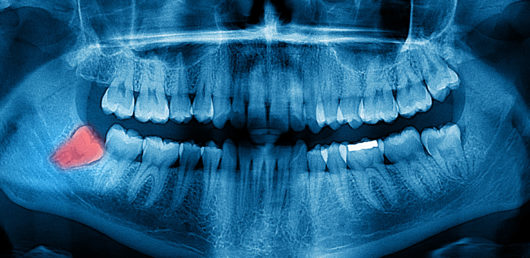

En muchas ocasiones, las muelas del juicio, o cordales, son invisibles, eso sucede cuando están impactadas, es decir, atrapadas bajo la encía o atascadas con algún obstáculo, una situación que inicialmente puede no representar ninguna molestia, pero que con el paso del tiempo puede dar paso a muchas complicaciones.

Por ello, es necesario que cuando se alcanza la edad en la que normalmente erupcionan estas muelas (entre los 17 y los 25 años) se vayan haciendo pruebas de control (radiografías) para ver la evolución de estas piezas dentales.

¿Cómo se diagnostica una muela del juicio impactada?